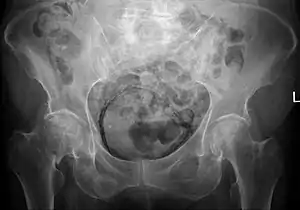

| Emphysematous cystitis as incidental finding in a case of hip fracture on the right | |

Due to the atypical presentation and rarity of the infection, it takes a physician longer to diagnose than more common types of bladder infections. Diagnosis requires a personalized investigation with consideration to risk factors and symptoms.[6] Radiology of the abdominal or pubic region has proven to be an important tool in reaching a definitive diagnosis of conditions causing gas in the urinary tract. Computer tomography, or CT scans, are of most help due to their high sensitivity in detecting gas and air bubbles.[10] However, radiology is normally not the first tool used to diagnose. Most diagnoses are made by chance after imaging examination.[7] Sometimes, even when patients don't show symptoms, their Emphysematous cystitis infection level can be very advanced already.[5] Gas in the bladder wall will often have the appearance of cobblestone or a “beaded necklace” with the use of conventional radiography.[7] Delayed diagnosis can lead to a severe infection, extension of the uterus, rupturing of the bladder, and death. Emphysematous cystitis has an overall mortality rate of 7%. However, surgery is only considered in severe cases where the disease progresses involving the ureters, kidneys, or adrenal glands. When required, surgery may be extensive.[5]